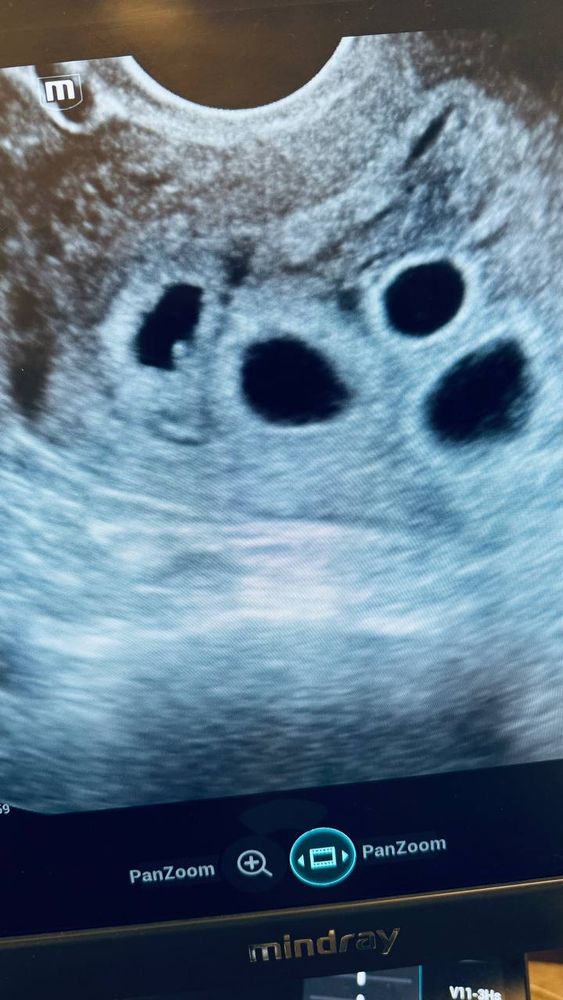

И далее я помню только начало... Потому что мне сказали "У вас 4 плодных яйца. 3 из них точно имеют сердцебиение" все что я смогла ответить "а чем я их кормить буду???". Далее я истерила...

На данный момент мы уже сходили в клинику где делали ЭКО. Сделали высокоточное узи в консилиуме врачей, включая генетика. 4 эмбриона. 3 сердцебиения. 1н меньше других и сердцебиение не различимо.

Клиника провела всю ревизию материалов. Наши эмбрионы, фото-камеры и так далее с узи, пункции, подсадки, замороженные эмбрионы. Откуда взялось +3 эмбриона никто не знает. Видно одно - это не близнецы. Каждое плодное яйцо индивидуально, согласно размерам оболочек